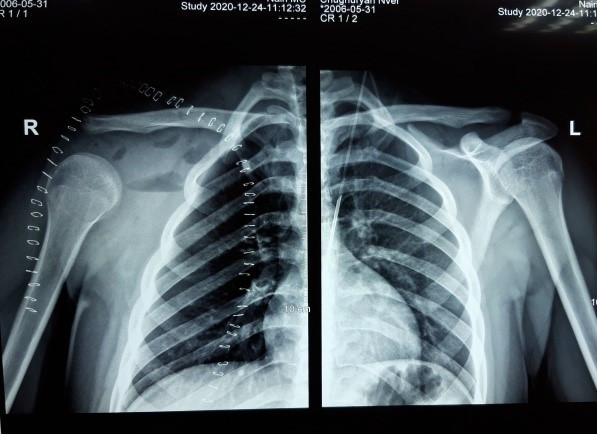

После курсов неоадъювантной химиотерапии удалось полностью нейтрализовать мягкотканный компонент опухоли и провести радикальное вмешательство, сохранив акромиальный участок ключицы со связками, к которой были фиксированы остальные части суставной сумки плеча.

Первым требованием в онкологии является радикальность вмешательства, а вторым – восстановить то, что было удалено. После тотального удаления лопатки практически невозможно иметь превосходные функциональные результаты, поскольку удаляется вся суставная поверхность. А в эстетическом плане весьма важно предотвращение провисания конечности. В нашем случае удалось получить такой конечный вид плечевого пояса, который полностью удовлетворил больного и функционально, и эстетически.

Рисунок 2. После операции имеем отличный эстетический результат